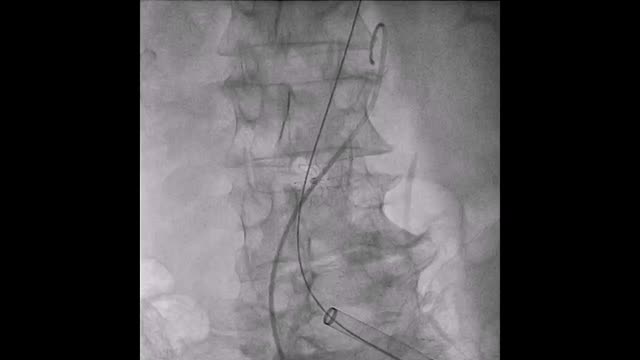

El paciente se traslada a la sala de hemodinamia donde se intenta la extracción del dispositivo. Se utilizan diferentes catéteres lazo de 10, 25 y 30 mm, así como lazos de fabricación con guías largas y cortas intentando movilizar el dispositivo desde diferentes accesos vasculares (acceso bifemoral 6 y 18 Fr y radial 6 Fr) (figuras de la 1 a la 4). Se produce como complicación disección de aorta abdominal con extensión a arteria ilíaca común derecha (figuras 5 y 6) y pérdida total del flujo en extremidad inferior ipsilateral con signos y síntomas de isquemia arterial aguda, por lo que el paciente es trasladado de forma urgente al quirófano de angiología y cirugía vascular. Se realiza disección de aorta abdominal infrarrenal vía laparotomía media con aortotomía longitudinal en el lugar de la localización del cuerpo extraño visualizándose el dispositivo migrado anclado a la íntima-media de la pared arterial. Se procede a su extracción y posteriormente se realiza cierre de aortotomía con parche de pericardio bovino fijando la disección y corrigiendo así el defecto (figuras de la 7 a la 9). El paciente sale de quirófano con pulso pedio bilateral y excelente perfusión distal.